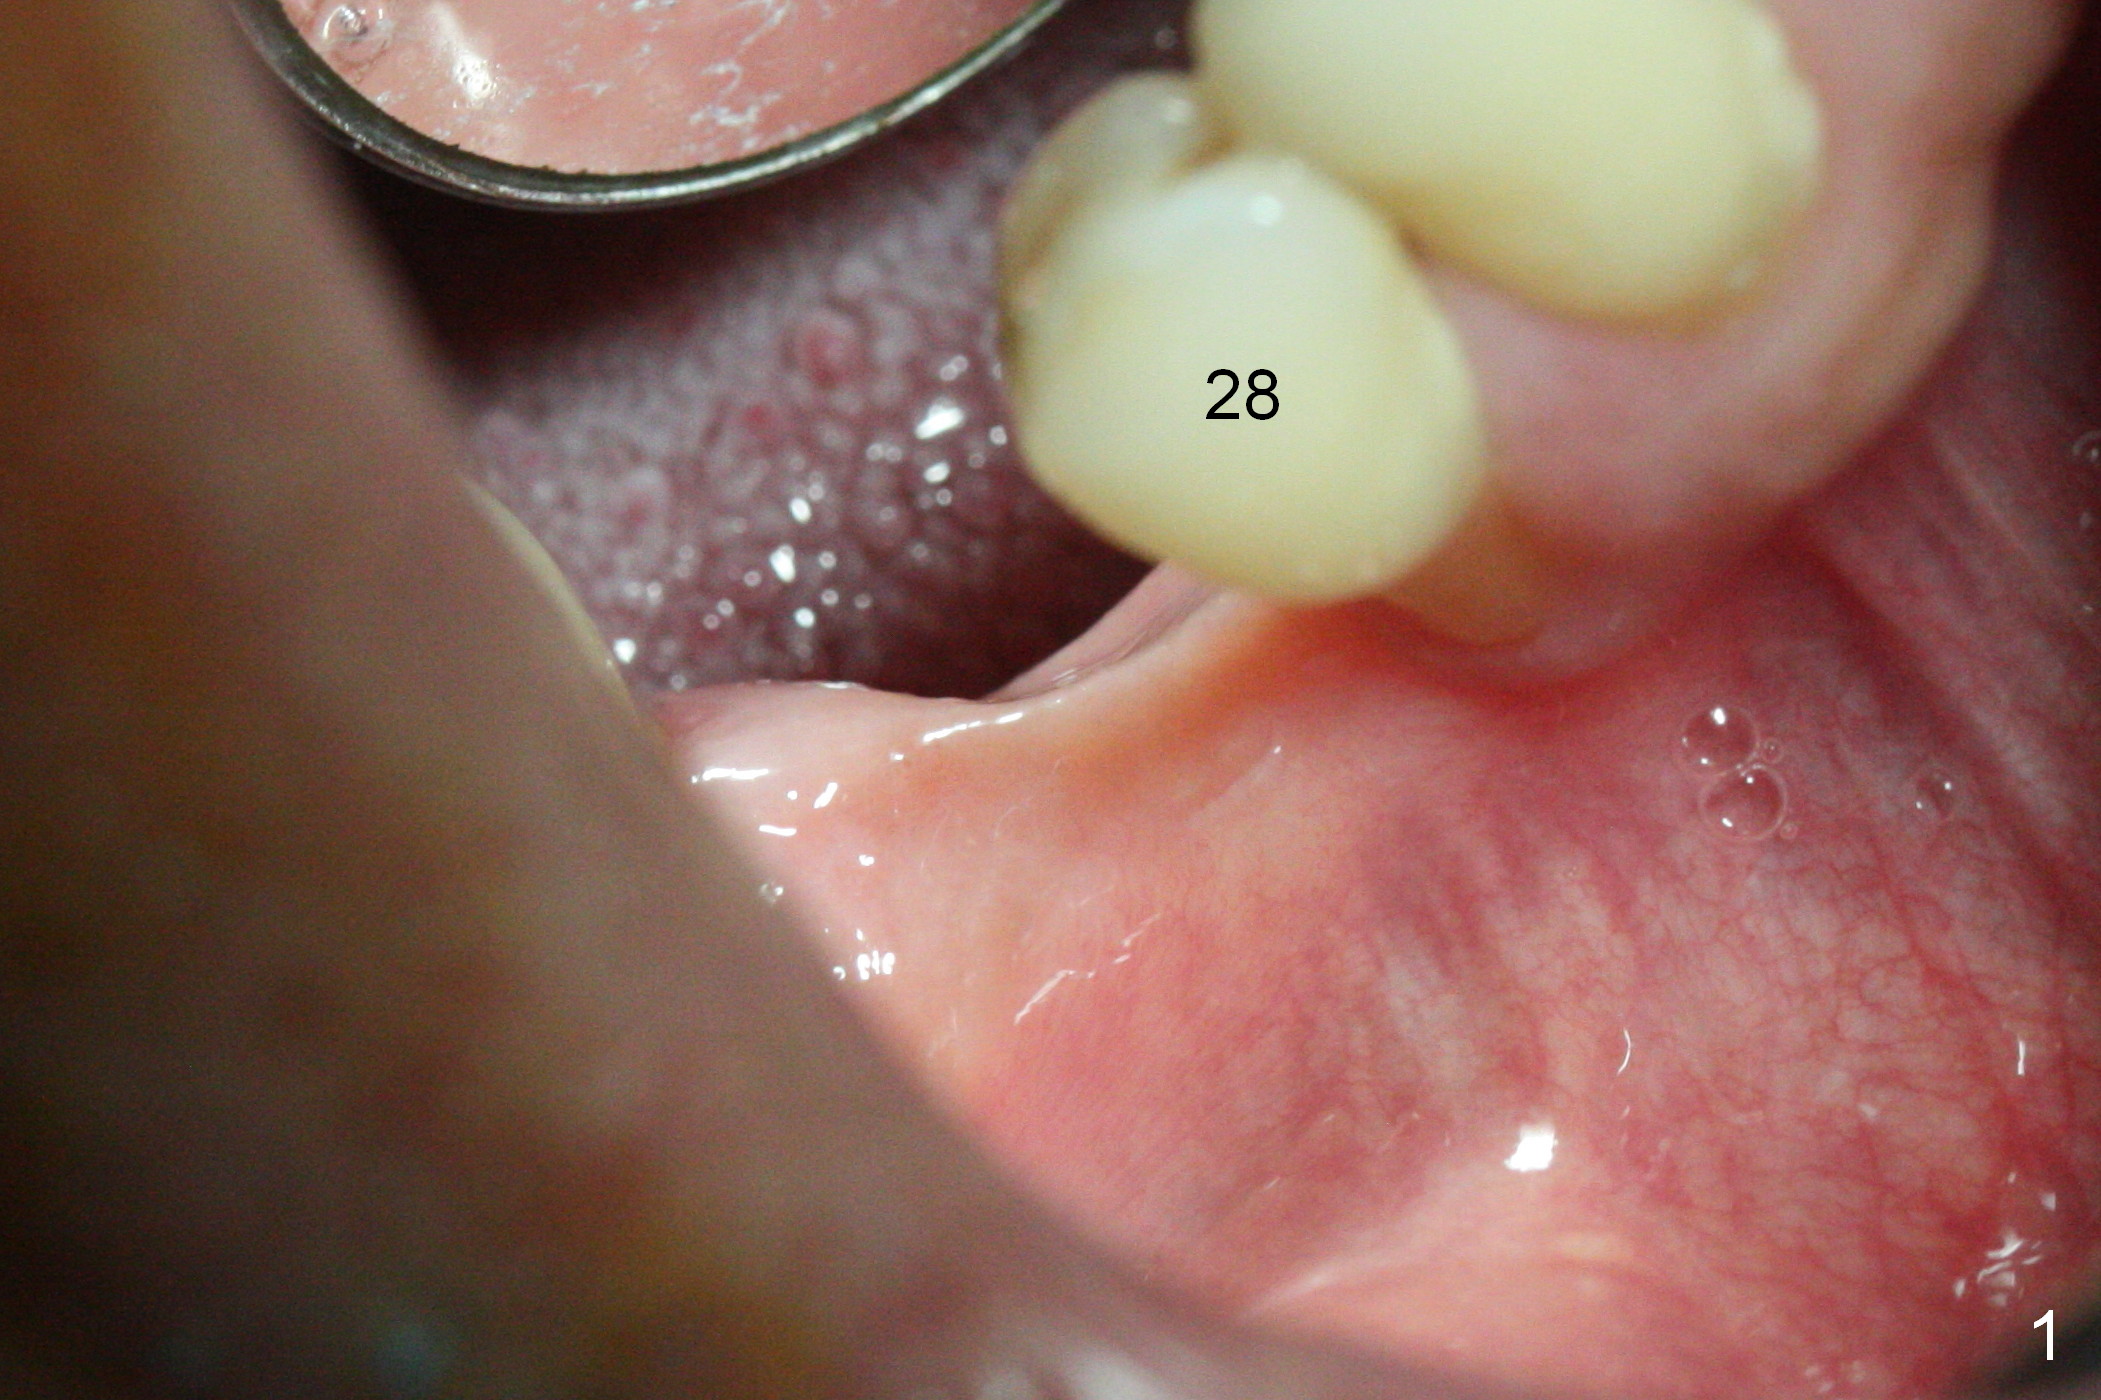

The wide mesiodistal space at #29 is most likely due to congenital missing permanent tooth (i.e., deciduous molar retention before extraction 34 years ago). The patient is now 62 years old. In fact the buccolingual width is not so narrow (Fig.1). After incision, the ridge is approximately 5 mm. Two osteotomies are established with 1.2 mm drill at 8 mm mesially and 1.5 mm one at 10 mm distally (Fig.2). The apparent approximation of the mesial osteotomy to the Mental Loop (red dashed line) is related to X-ray angulation, since there is 1-2 mm separation when two of 2x10(2) mm 1-piece implants are placed (Fig.3,4). Insertion torques of the mesial and distal implants are less than 25 and 15 Ncm, respectively. In fact bone graft is placed around the distolingual root of the tooth #30 after calculus removal (Fig.4 <). Following reduction of the abutments, periodontal dressing is applied locally. The dressing dislodged 13 days postop (Fig.5). A provisional is going to be fabricated 4 weeks postop when the wound heals (Fig.6). No bone loss is observed 4 months postop (Fig.7).